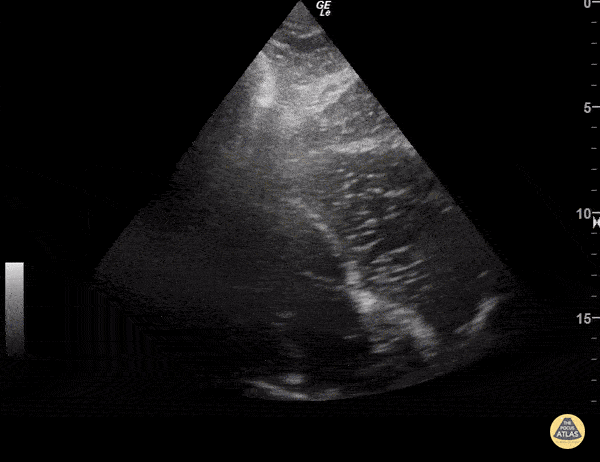

Left Ventricular Dysfunction - Asystole

Fluid bubbles sitting in right ventricle without any signs of cardiac activity. Imaging taken during cardiac arrest resuscitation pulse check. Sukh Singh, MD